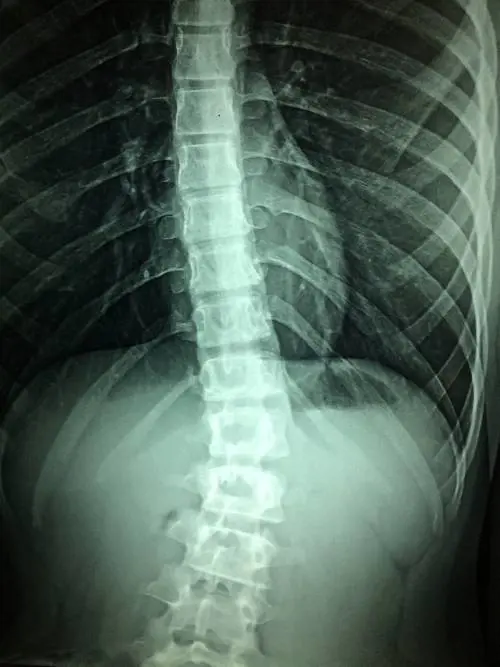

Grazie a una terapia genica in grado di riattivare le fibre nervose, alcuni topi con lesione completa al midollo spinale sono tornati a camminare: ecco cosa dice lo studio che accende una nuova speranza per l'uomo

I risultati dello studio fanno ben sperare. In futuro potrebbero essere messi a punto nuovi trattamenti farmacologici e persino una terapia genica